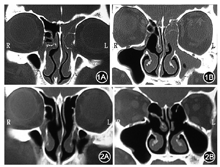

内镜额窦手术是内镜鼻窦手术中较为复杂的手术[5],主要原因有两个:一是该区域的解剖较为复杂,受各类额筛气房的影响,变异较多;二是该区域内有较为重要的解剖结构,如筛前动脉、眼眶和颅底等。21世纪初,随着内镜解剖和CT影像学研究的进展,相关解剖已较为清晰[6,7]。有研究表明,内镜鼻窦手术后额筛气房开放不充分是额窦炎症迁延的独立危险因素,从一个侧面说明术中解剖开放额筛气房的重要性(图1,图2)[8]。